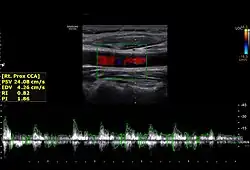

The condition and health of the common carotid arteries is usually evaluated using Doppler ultrasound, CT angiography or phase contrast magnetic resonance imaging (PC-MRI).

Typically, blood flow velocities in the common carotid artery are measured as peak systolic velocity (PSV) and end diastolic velocity (EDV).

In a study of normative men aged 20–29 years, the average PSV was 115 cm/sec and EDV was 32 cm/sec. In men 80 years and older, the average PSV was 88 cm/sec and EDV was 17 cm/sec.[7]

Right proximal common carotid artery normal spectral flow with PSV and EDV measurements by using doppler ultrasound